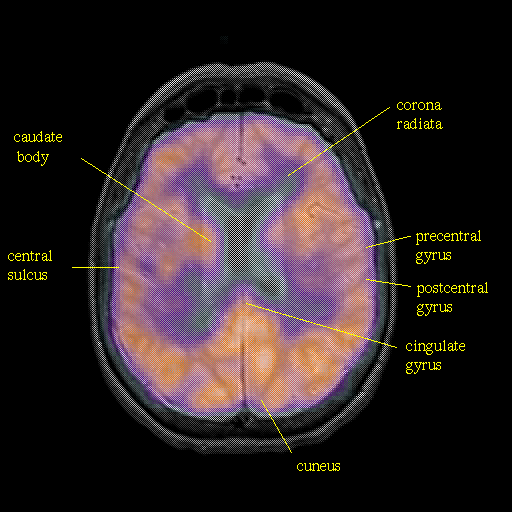

overlay : Slice 34

Slice 34

Pointers

Labeled